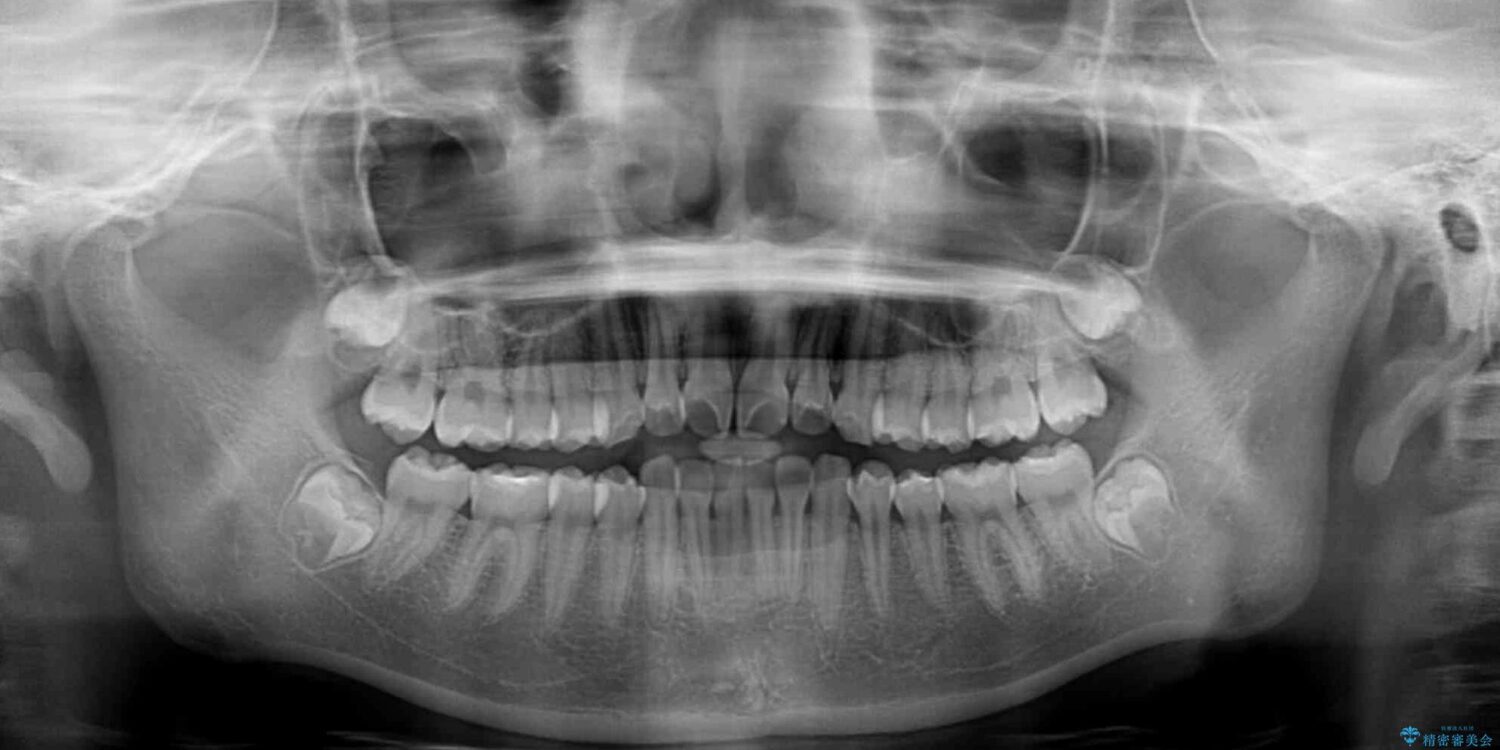

上下前歯のねじれを気にして来院された患者様です。

ワイヤー矯正でもマウスピース矯正でも対応可能でしたが、マウスピース矯正の自己管理が面倒であること、上顎前歯の捻転が著しいことから、ワイヤー矯正での治療を希望されました。

治療前

• インビザラインは使える自信がない ワイヤー装置にて矯正治療 治療前画像